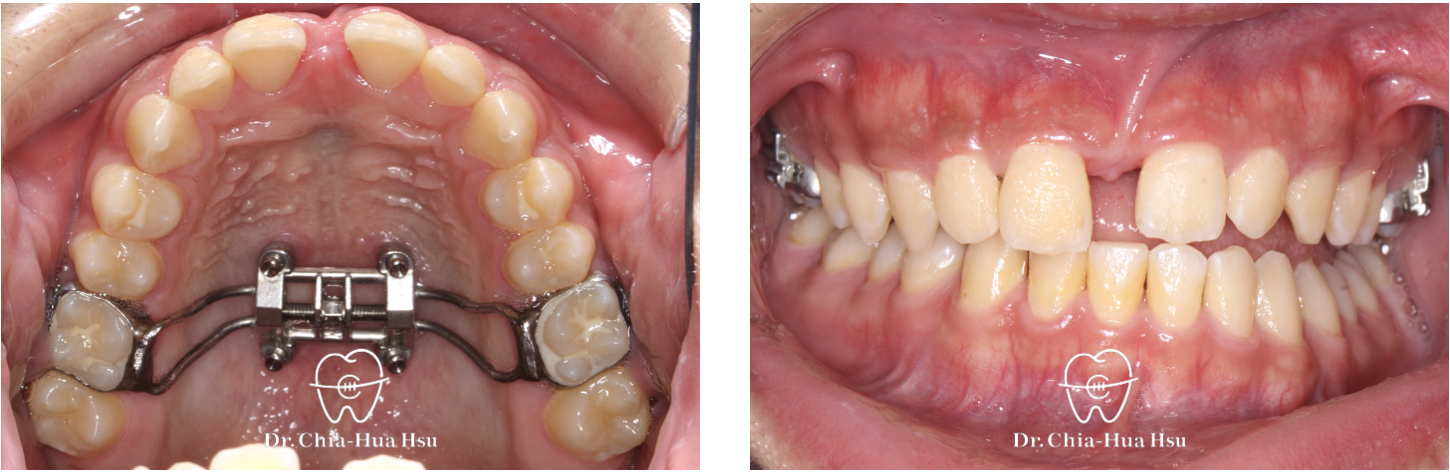

上顎擴弓:青少年使用骨釘輔助上顎擴弓器,將過窄的上顎牙弓撐寬。

治療中

• 治療過程:治療過程使用『陰陽線』,來改善咬合平面歪斜的問題。

• 矯正小知識:『陰陽線』是利用特殊設計的 Beta-titanium arch wire (TMA) 線材(一條往上一條往下,像是太極的陰陽)來調整上顎咬合面的傾斜,改善患者的咬合面傾斜問題,並避免手術的痛苦。